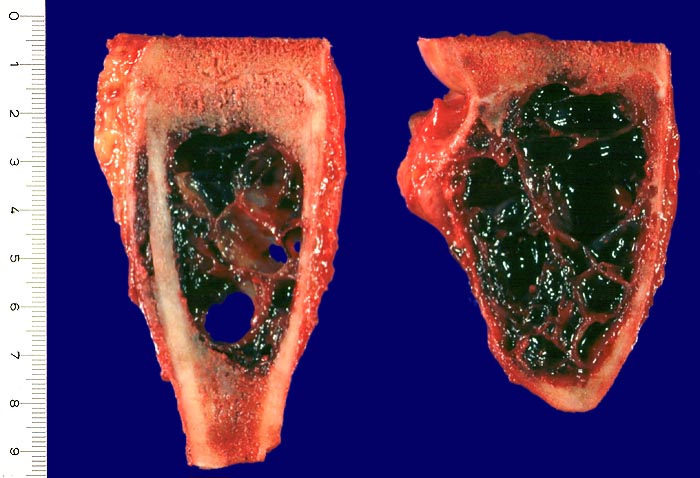

Die aneurysmatische Knochenzyste zählt zu den gutartigen tumorartigen Läsionen. Sie ist eine schnellwachsende, lokal aggressive, intramedullär gelegene Läsion, welche zu einer Knochenauftreibung führt. AKZ können primär oder sekundär auftreten (zusammen mit einem Chondroblastom, einem Chondromyxoid Fibrom, einem Riesenzelltumor, einer fibrösen Dysplasie oder einem Osteosarkom (> 2090)).

Die AKZ ist charakterisiert durch kavernöse Bluthohlräume mit dazwischengelegenen zellreichen Septen unter Einschluss von Riesenzellen. Da sekundäre AKZ häufig sind, muss das gesamte Material histologisch untersucht werden.

Radiologisch (> 5034) (> 5036) (> 5035) führt die AKZ zu einer exzentrischen scharf begrenzten gekammerten Osteolyse mit verdünnter vorgewölbter Kortikalis im Bereich der Metaphyse, seltener der Diaphyse. Die Therapie besteht in der Kurettage.

• Pseudozystische kavernöse Bluthohlräume eingebettet in Skelettmuskulatur.

Makroskopie